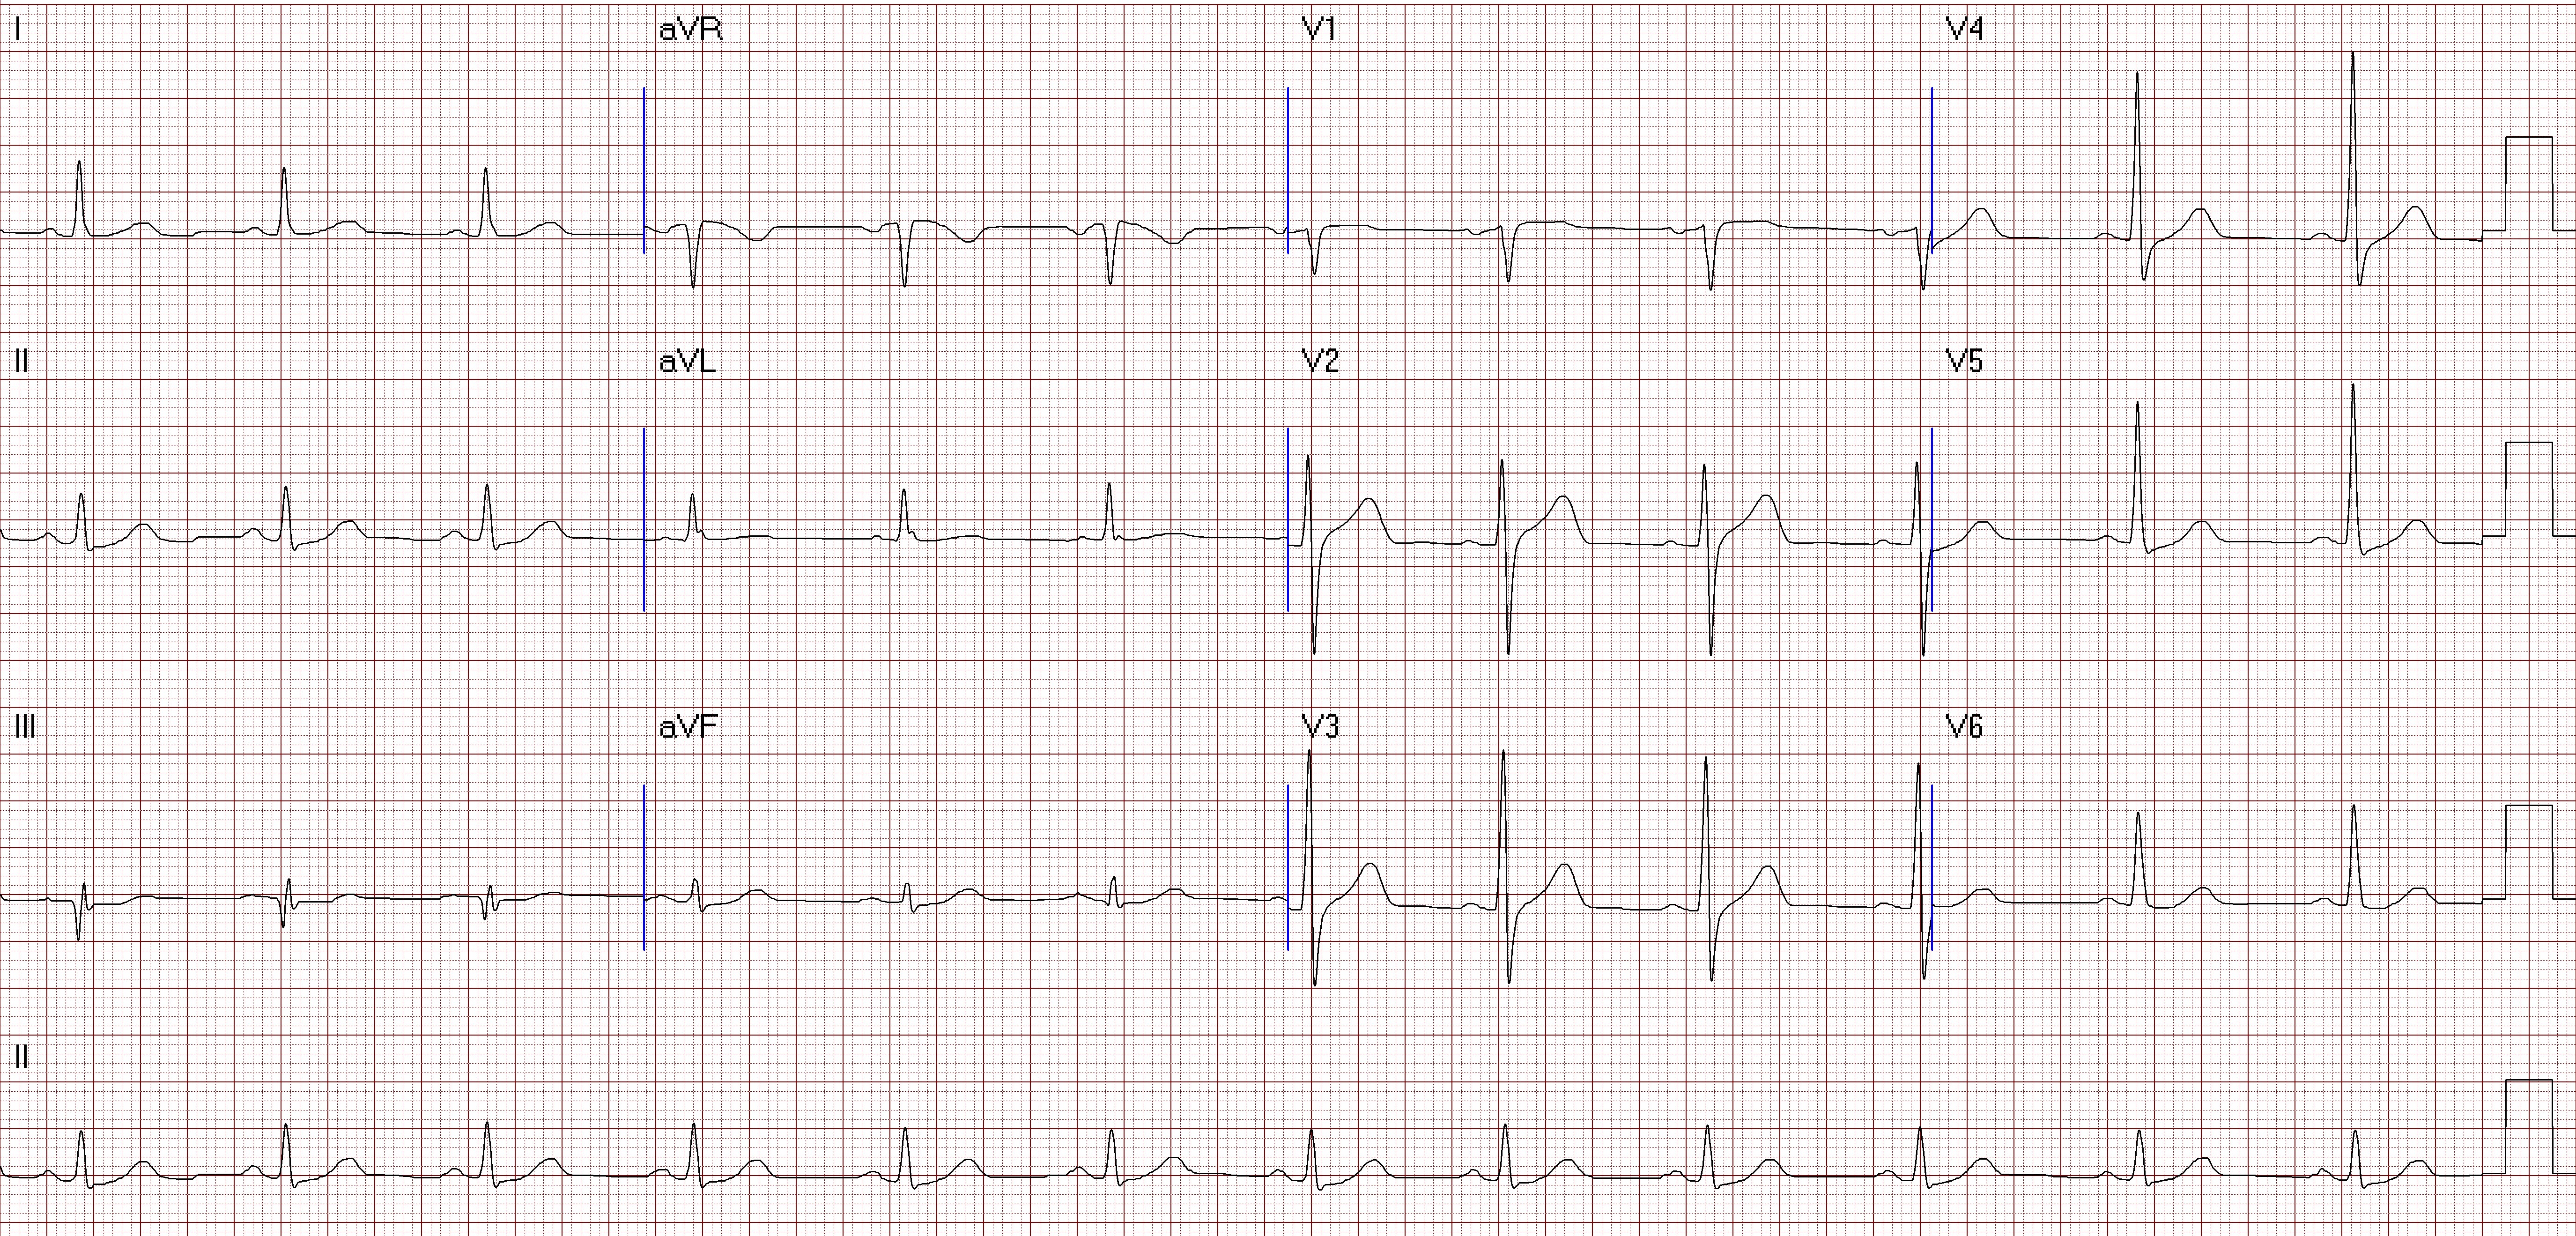

A 55-year-old man who has medical history of hyperlipidemia and personal history of cigarette smoking for decades came to our outpatient clinic for intermittent chest tightness for about 10 years, which got worsened when exercise. Also, short of breath after walking or taking little exercise was stated by the patient. On review, physical examination had no significant finding. An ECG showed sinus rhythm with Q wave over lead III.

Treadmill's exercise ECG was performed, and showed ST depression over inferior and lateral leads. The exam was terminated before 90% predicted heart rate achieved(Bruce stage 2) due to dyspnea and the patient cannot follow up. Echocardiogram was also arranged, and showed mild AR, TR, mild to moderate MR and normal LV systolic wall motion with LVEF 55%. Chest X ray found no definite evidence of significant active lung lesion or cardiomegaly.